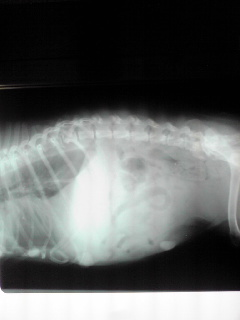

状態、非常に悪く、元気・食欲なく、痩せているにもかかわらず、お腹は膨れて、呼吸もままならず、X線では胸水が溜まり、その性で心臓もよく写っていない状況でした。